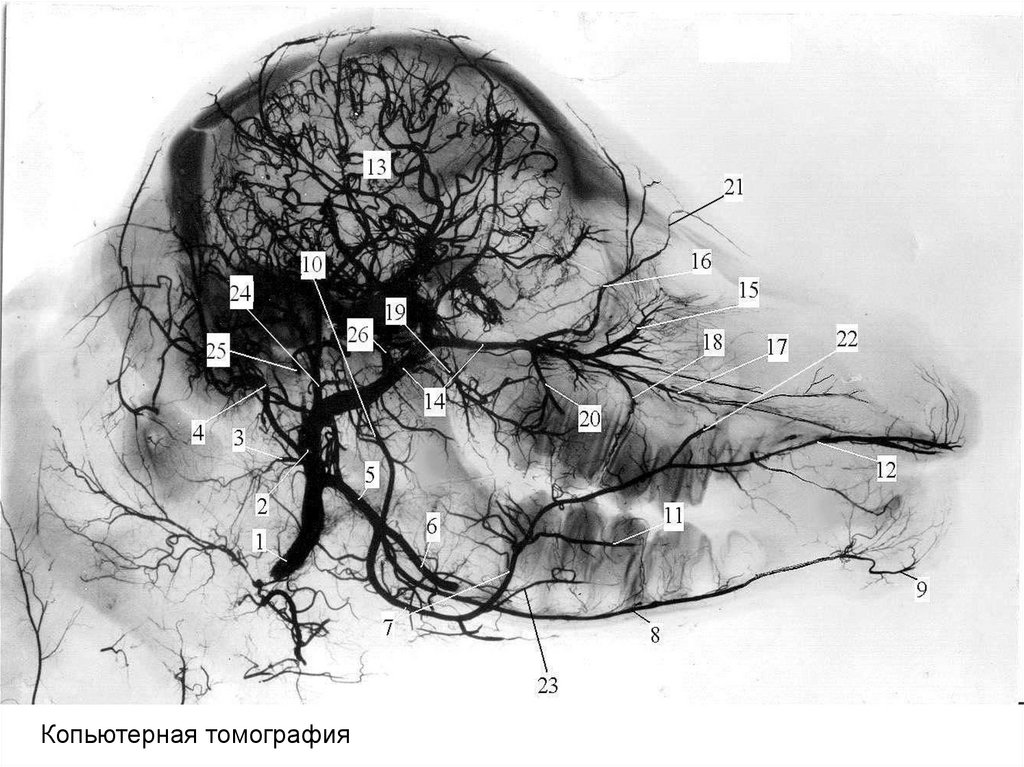

Копьютерная томография